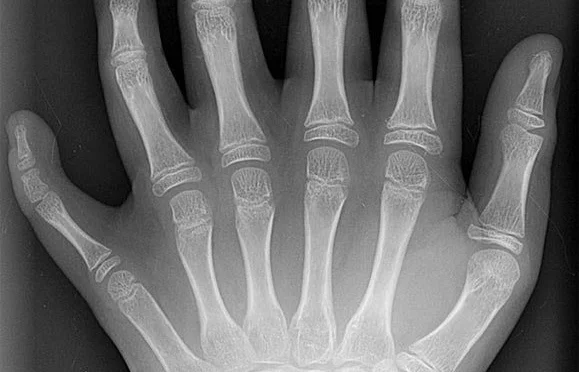

Рентгеновский снимок шестипалой кисти с полностью сформированными пальцами